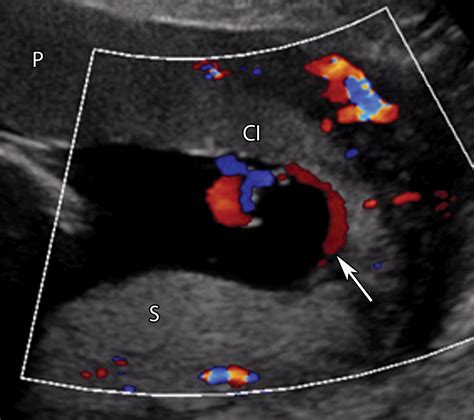

Detecting an Accessory Lobe Placenta typically involves ultrasound imaging. During routine prenatal ultrasounds, healthcare providers can identify the presence of an accessory lobe by observing the placental structure and its connections. Ultrasound imaging allows for the visualization of the vascular bridge that connects the accessory lobe to the main placenta, confirming its presence.

In some cases, additional monitoring techniques such as Doppler ultrasound may be used to assess blood flow through the vascular bridge connecting the accessory lobe to the main placenta. This helps to ensure that the fetus is receiving adequate nutrients and oxygen.